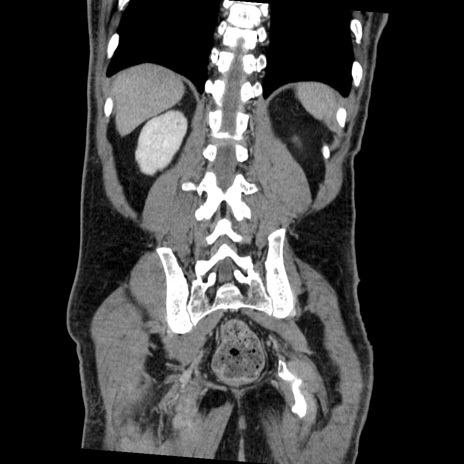

症例22(冠状断像)

【症例】50歳代男性

【主訴】腹痛

【現病歴】AVMからの被殻出血のため回復期リハ病棟入院中。 本日午後3時頃急に下腹部痛が出現した。

【既往歴】AVM、被殻出血、虫垂炎、高血圧

【身体所見】意識晴明、左半身不全麻痺、会話の理解は良好、36.5°C、腹部:膨隆、全体に板状硬、下腹部正中に圧痛点あり、反跳痛-、筋性防御不明、右下腹部にope scar

【データ】WBC 9400、CRP 0.06

横断像